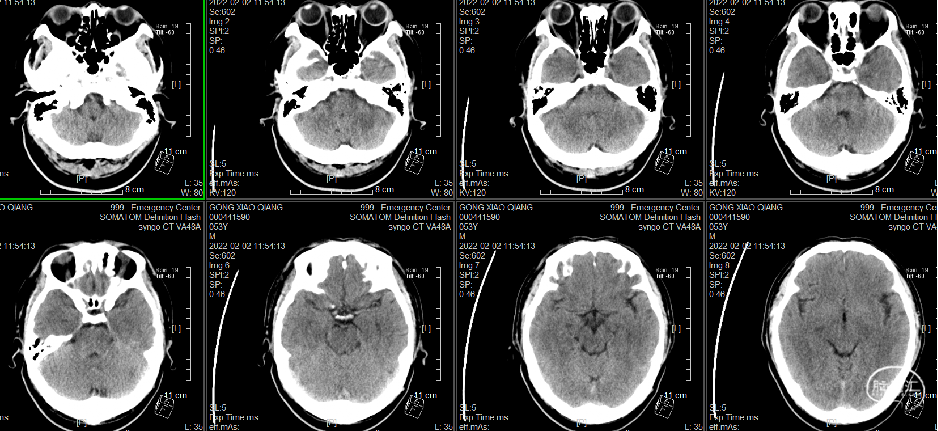

入院头颅CT(2022-2-2)

头颅CT:未见明确异常,建议MRI检查。